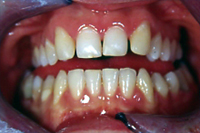

In der gleichen Sitzung hat sie dem Patienten auch die Oberkieferfront verschönert. Wegen eines genetisch angeborenen Defekts fehlen die seitlichen Schneidezähne; neben den mittleren Schneidezähnen folgen also direkt die spitzigen Eckzähne, wie in Abb. 3 gezeigt. Durch Ansetzen von Kompostifüllungen dank adhäsiver Technik wurden die Eckzähne formlich - ohne geringstes Beschleifen - zu natürlichen, seitlichen Schneidezähnen ummodelliert. Wie Abb. 4 zeigt, wurde dadurch der Schneidekantenverlauf viel harmonischer.